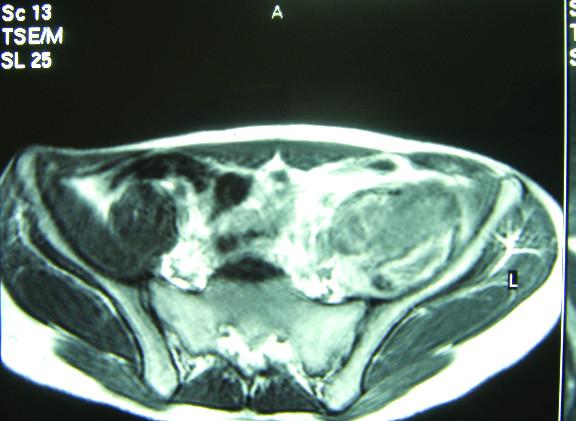

Iliopsoas pseudotumour is a serious complication of haemophilia. We present the case of a 20-year-old male patient with a six-month history of left leg weakness, limitation of movement and wasting of the muscles. Clinically he was diagnosed as having a psoas muscle rhabdomyosarcoma. During a computed tomography (CT) scan-guided Tru-cut biopsy he developed a serious and life-threatening bleeding from a retroperitoneal muscular haematoma. The patient underwent laparotomy prior to his final diagnosis of an Iliopsoas pseudotumour, which is a serious, as well as rare, complication of haemophilia.

髂腰肌假瘤是血友病的一种严重并发症。我们报告一例20岁男性患者,有六个月左腿无力、活动受限及肌肉萎缩病史。临床上他被诊断为腰大肌横纹肌肉瘤。在计算机断层扫描(CT)引导下进行粗针穿刺活检时,他因腹膜后肌肉血肿出现了严重的、危及生命的出血。在最终诊断为髂腰肌假瘤之前,患者接受了剖腹手术,髂腰肌假瘤是血友病一种严重且罕见的并发症。